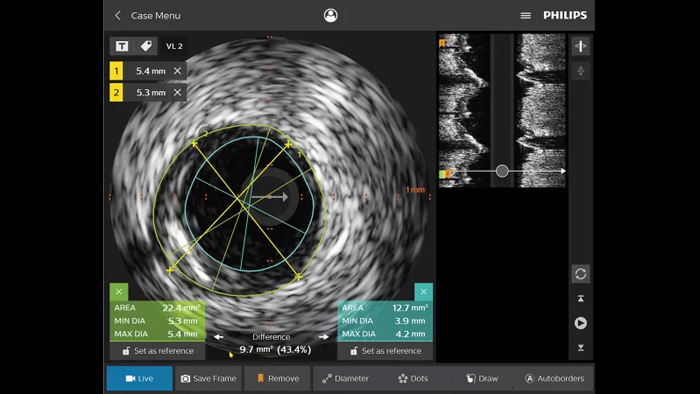

El ultrasonido intravascular (IVUS) es una tecnología de obtención de imágenes basada en catéteres que permite a los médicos visualizar los vasos sanguíneos desde adentro hacia afuera para ayudar a evaluar la presencia y el alcance de la enfermedad. IVUS ayuda a decidir, guiar y confirmar el tratamiento intervencionista adecuado para cada paciente.

IntraSight proporciona más información mediante las modalidades iFR/FFR e IVUS y el angiograma, controlado en la pantalla táctil de la mesa. Se basa en una plataforma básica capaz de agregar rápidamente innovaciones a su laboratorio.